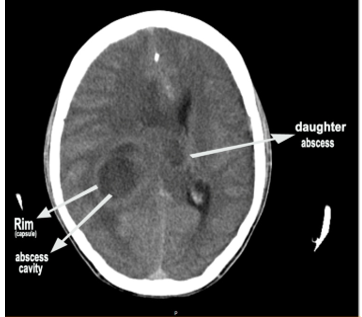

Figure 5: CT brain showing the large abscess cavity in the parietal lobe with mild midline shift in a 16 –year old boy with Tetralogy of Fallot. Upper arrow showing the Rim (capsule) and the lower arrow showing the abscess cavity.

Figure 6: CT brain showing the large abscess cavity in the parietal lobe with “ daughter abscess” in the lower part (lowest arrow) with moderate midline shift in a 16 –year old boy with Tetralogy of Fallot.

Figure 7: CT brain showing the large abscess cavity in the parietal lobe with small “daughter abscess” in the upper part (right arrow) in a 16 –year old boy with Tetralogy of Fallot.

CT (computed tomography) brain revealed a large abscess cavity in the parietal region as in Figures 5, 6 and 7. The abscess was aspirated via burr-hole and cultures were found to be negative. He was given ceftriaxone 1g IV twice daily, amickacin 500 mg IV twice daily with tablet phenytoin sodium 100 mg twice daily for 2 weeks. He was symptom free and advised periodic follow up. On 1 year follow up, the patient was asymptomatic without any sequelae and advised corrective surgery for the cardiac anomaly at the earliest.

Brain abscess is an encapsulated inflammation and can be easily diagnosed by CT scan. The CT appearance of an abscess is that of a well-defined hypodense area showing ring enhancement and accompanied by extensive perifocal edema and mass effect. The ring enhancement on the CT scan surrounding a central necrotic cavity as in Figure 5 is an abscess. The appearance of enhancing rim, the capsule of the abscess enhances and it is variable. The rim is formed probably by collagen and inflammation due to free radicals and micro hemorrhages in the abscess. The abscess tends to grow towards white matter, away from the better vascularized grey matter, with thinning of the medial wall. The preferential deposits of collagen on the outer edge of the abscess is thought to be due to the vascularization of grey matter. The zone of inflammation is significantly thicker in tuberculous as compared to pyogenic abscess. The neuroimaging features of brain abscess vary with lesion stage as shown in Table 3. During the cerebritis stage (local suppurative encephalitis or immature abscess), ring enhancement may be absent or incomplete. Abscesses with a more nodular rim are often mistaken for neoplasm. Brain abscesses tend to have a smooth, thin-walled capsule and it is more irregular in tumors. In contrast to tumor, the abscess rim is typically thicker near the cortex and thinnest near the ependyma. Early capsule stage is characterized by formation of a distinct collagenous capsule, which is well delineated, relatively thin, uniform and continuous. The uniformely enhancing capsule is typical of a mature abscess. The abscess gradually shrink, peripheral edema diminishes and then disappears in the late capsule stage.

The apparent budding of smaller, ‘daughter’ lesion from the main mass is called as “daughter abscess”. In about 50% of cases, the medial wall of an abscess is thinner than the lateral one and is thought to be due to the relatively poor vascular supply of the white matter. This explains the tendency of abscess to rupture into the ventricles and the development of secondary abscesses (daughter abscess) medially [45] may be seen near the primary lesion as in Figures 6 and 7. In deep seated, multiloculated and periventricular abscesses, a reduction of 1 mm in the distance between the ventricle and brain abscess wall increases the rupture rate by 10% [46]. Smooth, < 5>